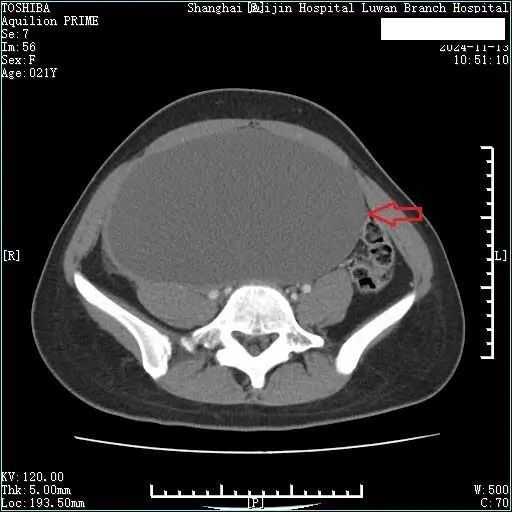

为尽可能在最大限度保留生育功能的基础上切除肿瘤,王明亮教授团队联合妇科朱岚教授团队一起对小宁的病情做了评估,制定了详细的手术方案。术前CT评估显示中下腹部见巨大囊性肿块,大小为18.7*10.8*23.4cm。

在入院的第三天小宁接受了手术治疗,王明亮教授团队联合妇科朱岚主任团队精心设计了下腹部不到10cm的远小于肿块大小的切口,先对肿块进行抽液减压,抽出囊液约2400ml后再进行探查,肿块来源于右侧卵巢。完整剥离肿瘤并且保留了右侧卵巢,最大限度地保留生育功能。